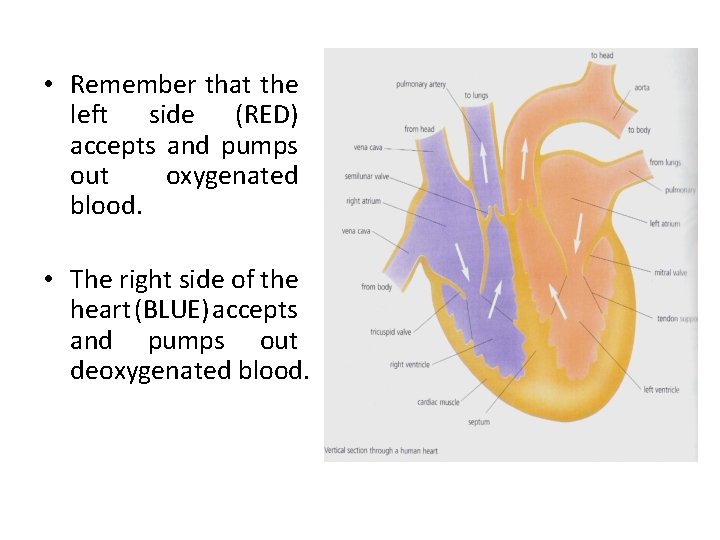

Internal Structure of the Heart • The heart has four chambers: the left and right atria (1 atrium) and the left and right ventricles. • The following diagram is the internal structure of the heart.

• Remember that the left side (RED) accepts and pumps out oxygenated blood. • The right side of the heart (BLUE) accepts and pumps out deoxygenated blood.

The Heart Summary Fist sized; found on left side. Consists of cardiac muscle fed by coronary arteries Left side pumps O 2 -rich blood to head and body; Right side pumps O 2 -poor blood to lungs Two upper atria, two lower ventricles Septum separates left and right sides ensuring diffusion gradient • Left ventricle thicker to pump blood all over body • Valves prevent back-flow of blood • • •

OXYGENATED BLOOD • This is blood that is rich in oxygen because it has recently left the lungs where the process of gaseous exchange occurred in order for the oxygen to diffuse into the blood vessels. • The LEFT side of the heart pumps oxygenated blood which is very red.

DEOXYGENATED BLOOD • This is blood that is depleted of oxygen because it has travelled around the body supplying the body cells with the oxygen. • The RIGHT side of the heart pumps deoxygenated blood which has a slightly blue colour.

Path of Oxygenated Blood • Pulmonary vein left atrium • Through mitral valve down into the left ventricle. • The ventricle then contracts forcing the mitral valve closed and opening the semilunar valve. • The blood then flows up into the aorta and around the body.

Path of Deoxygenated blood • Vena cava right atrium • Through tricuspid valve right ventricle. • Ventricle contracts, tricuspid valve closes, semilunar valve opens. • Blood flows to the pulmonary artery lungs.